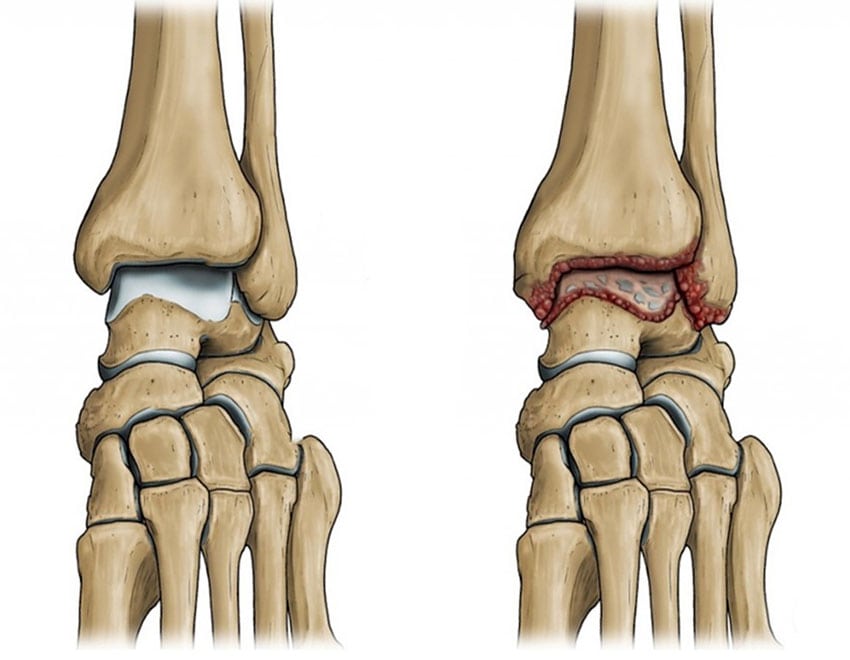

От степени поражения тканей, характера его течения зависят методы лечения. Эти факторы влияют на выраженность клинических проявлений воспалительной патологии. В основе ее патогенеза лежит поражение синовиальной оболочки сухожильного влагалища.

Асептическое заболевание развивается в результате микротравмирования сухожилия однотипными, монотонными движениями в сочетании с серьезными нагрузками на ногу. Возникает дефицит синовиальной жидкости, провоцирующий повреждение сухожильной капсулы в результате трения ее слоев. Если микротравмирование соединительнотканного тяжа продолжается, то продуцирование синовиальной жидкости, питающей сухожилие и выполняющей функцию амортизатора, постепенно снижается. Из-за ее недостатка возникают внутрикапсульные спайки, а поверхностный слой капсулы становится шероховатым.